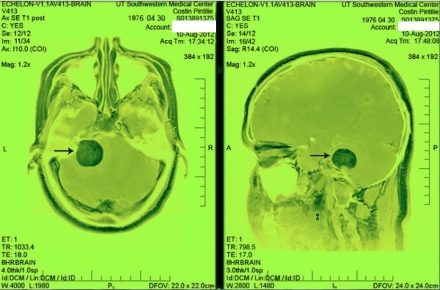

.Printr-un miracol, operația a fost un succes la care nici medicii nu se așteptau, iar respectiva tumoare „inoperabilă" a fost scoasă în totalitate.După operație însă, au existat și complicații, s-au dezvoltat și alte tumori, ceea ce înseamnă căîn ultima jumătate de an Costin a suferit șase operații pe creier.Acestea au fost realizate în Statele Unite ale Americii printr-o metodă revoluționară a medicinii, numită cyberknife. Cyberknife-ul este de fapt un sistem robotic folosit în foarte puține săli de operație din lume, care permite pacientului să fie operat de tumori pe creier, fără tăierea craniului. Faptul că un om a reușit să reziste fizic, dar mai ales emoțional atâtor greutăți și că acum se îndreaptă cu pași siguri spre vindecare, este un alt miracol.

A șasea, și ultima operație pe creier a avut loc pe data de 11 august 2012, iar diagnosticul a fost Primary CNS Lymphoma (tumoare a sistemului nervos central). În prezent Costin se recuperează după această ultimă operație, care a avut loc la UT Southwestern Medical Center în Dallas. Pentru această ultimă operație Costina fost băgat în coma indusă timp de 36 de ore, iar operația în sine a durat aproape 12 ore.Cu mai puțin de 60% șanse de supraviețuire și 8% șanse să nu rămână cu o dizabilitate, operația a fost un succes. Chiar și medicii au fost uimiți de propria lor măiestrie din sala de operație, și de faptul că nu a existat nici o complicație.